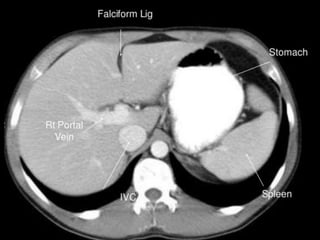

Liver:

 Lies mostly in the

right

hypochondrium, and

protected by rib

cage.

 Divided into two

lobes of unequal size

by the falciform

ligament.

CT cross sectional

anatomy.